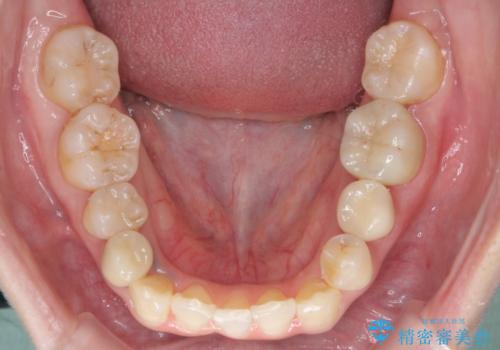

4本抜歯すると口元が下がりすぎてしまうため、下の前歯のみ1本抜歯および上顎の前歯が大きいため少し削らせてもらう提案をしました。

右上2番をしっかり並べるにはワイヤー矯正を上顎部分的に用いて、最後全体マウスピース治療を行いました。

上顎前歯は神経がない歯で色も変わってきていたためセラミックでかぶせています。